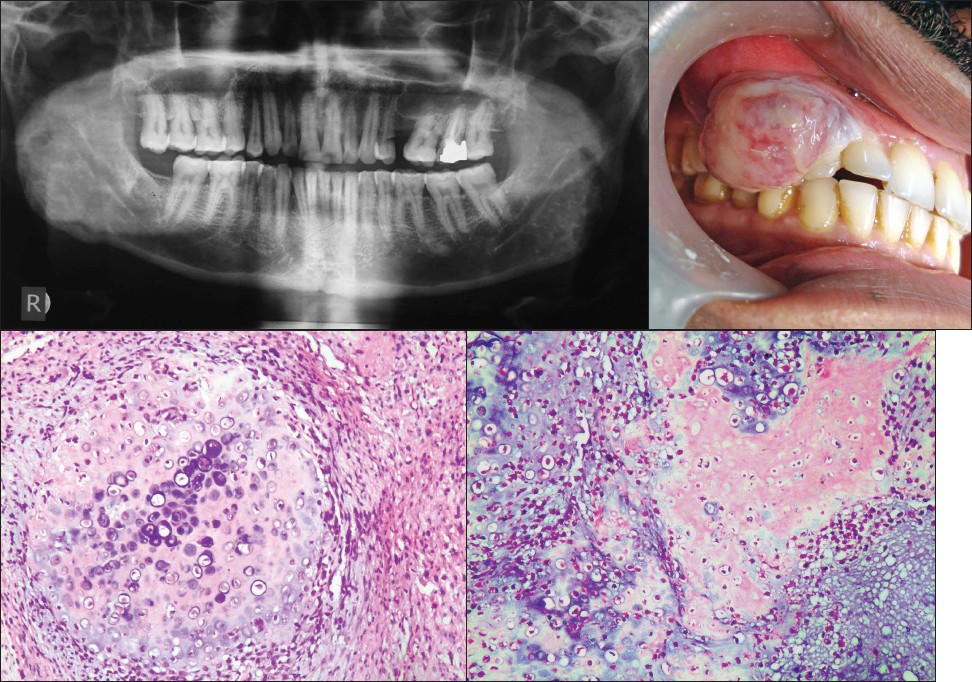

p>骨肉瘤是恶性度较高的肿瘤,约有5%发生于颌骨,下颌骨较上颌骨为多

【病案】存在吞咽困难的单发性下颌骨骨肉瘤